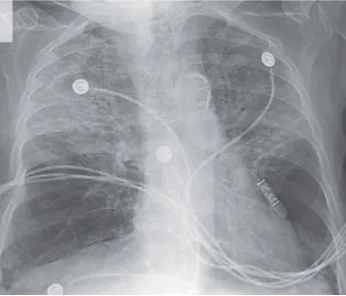

U0001F50E Resistência a Diuréticos na Doença Renal Crônica: o que fazer quando o edema não responde? O uso de diuréticos é rotina no manejo da congestão na DRC, mas o que explica os casos em que a resposta é ineficaz? Neste post, discutimos os principais mecanismos de resistência, estratégias de otimização do tratamento e quando considerar combinações ou abordagens alternativas.

Luís Sette

2 anos atrás